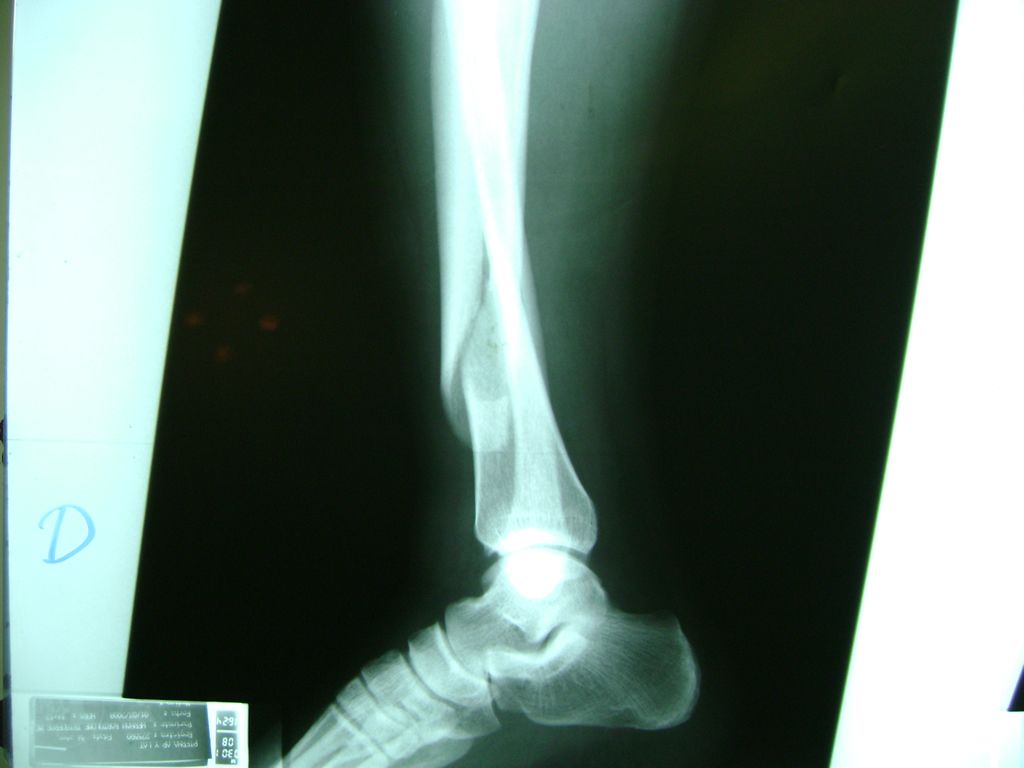

Cirugía de Tibia y Peroné

La mayor parte de las roturas implican a la parte proximal del hueso (parte del hueso próximo a la rodilla) o a la parte distal (parte del hueso cerca del tobillo).

Debido a la fina cobertura de piel que recubre la tibia y el peroné, las fracturas generalmente son abiertas, es decir, el hueso roto rasga la piel, atravesándola. Las fracturas de tibia y peroné generalmente se producen por un fuerte impacto o torsión.